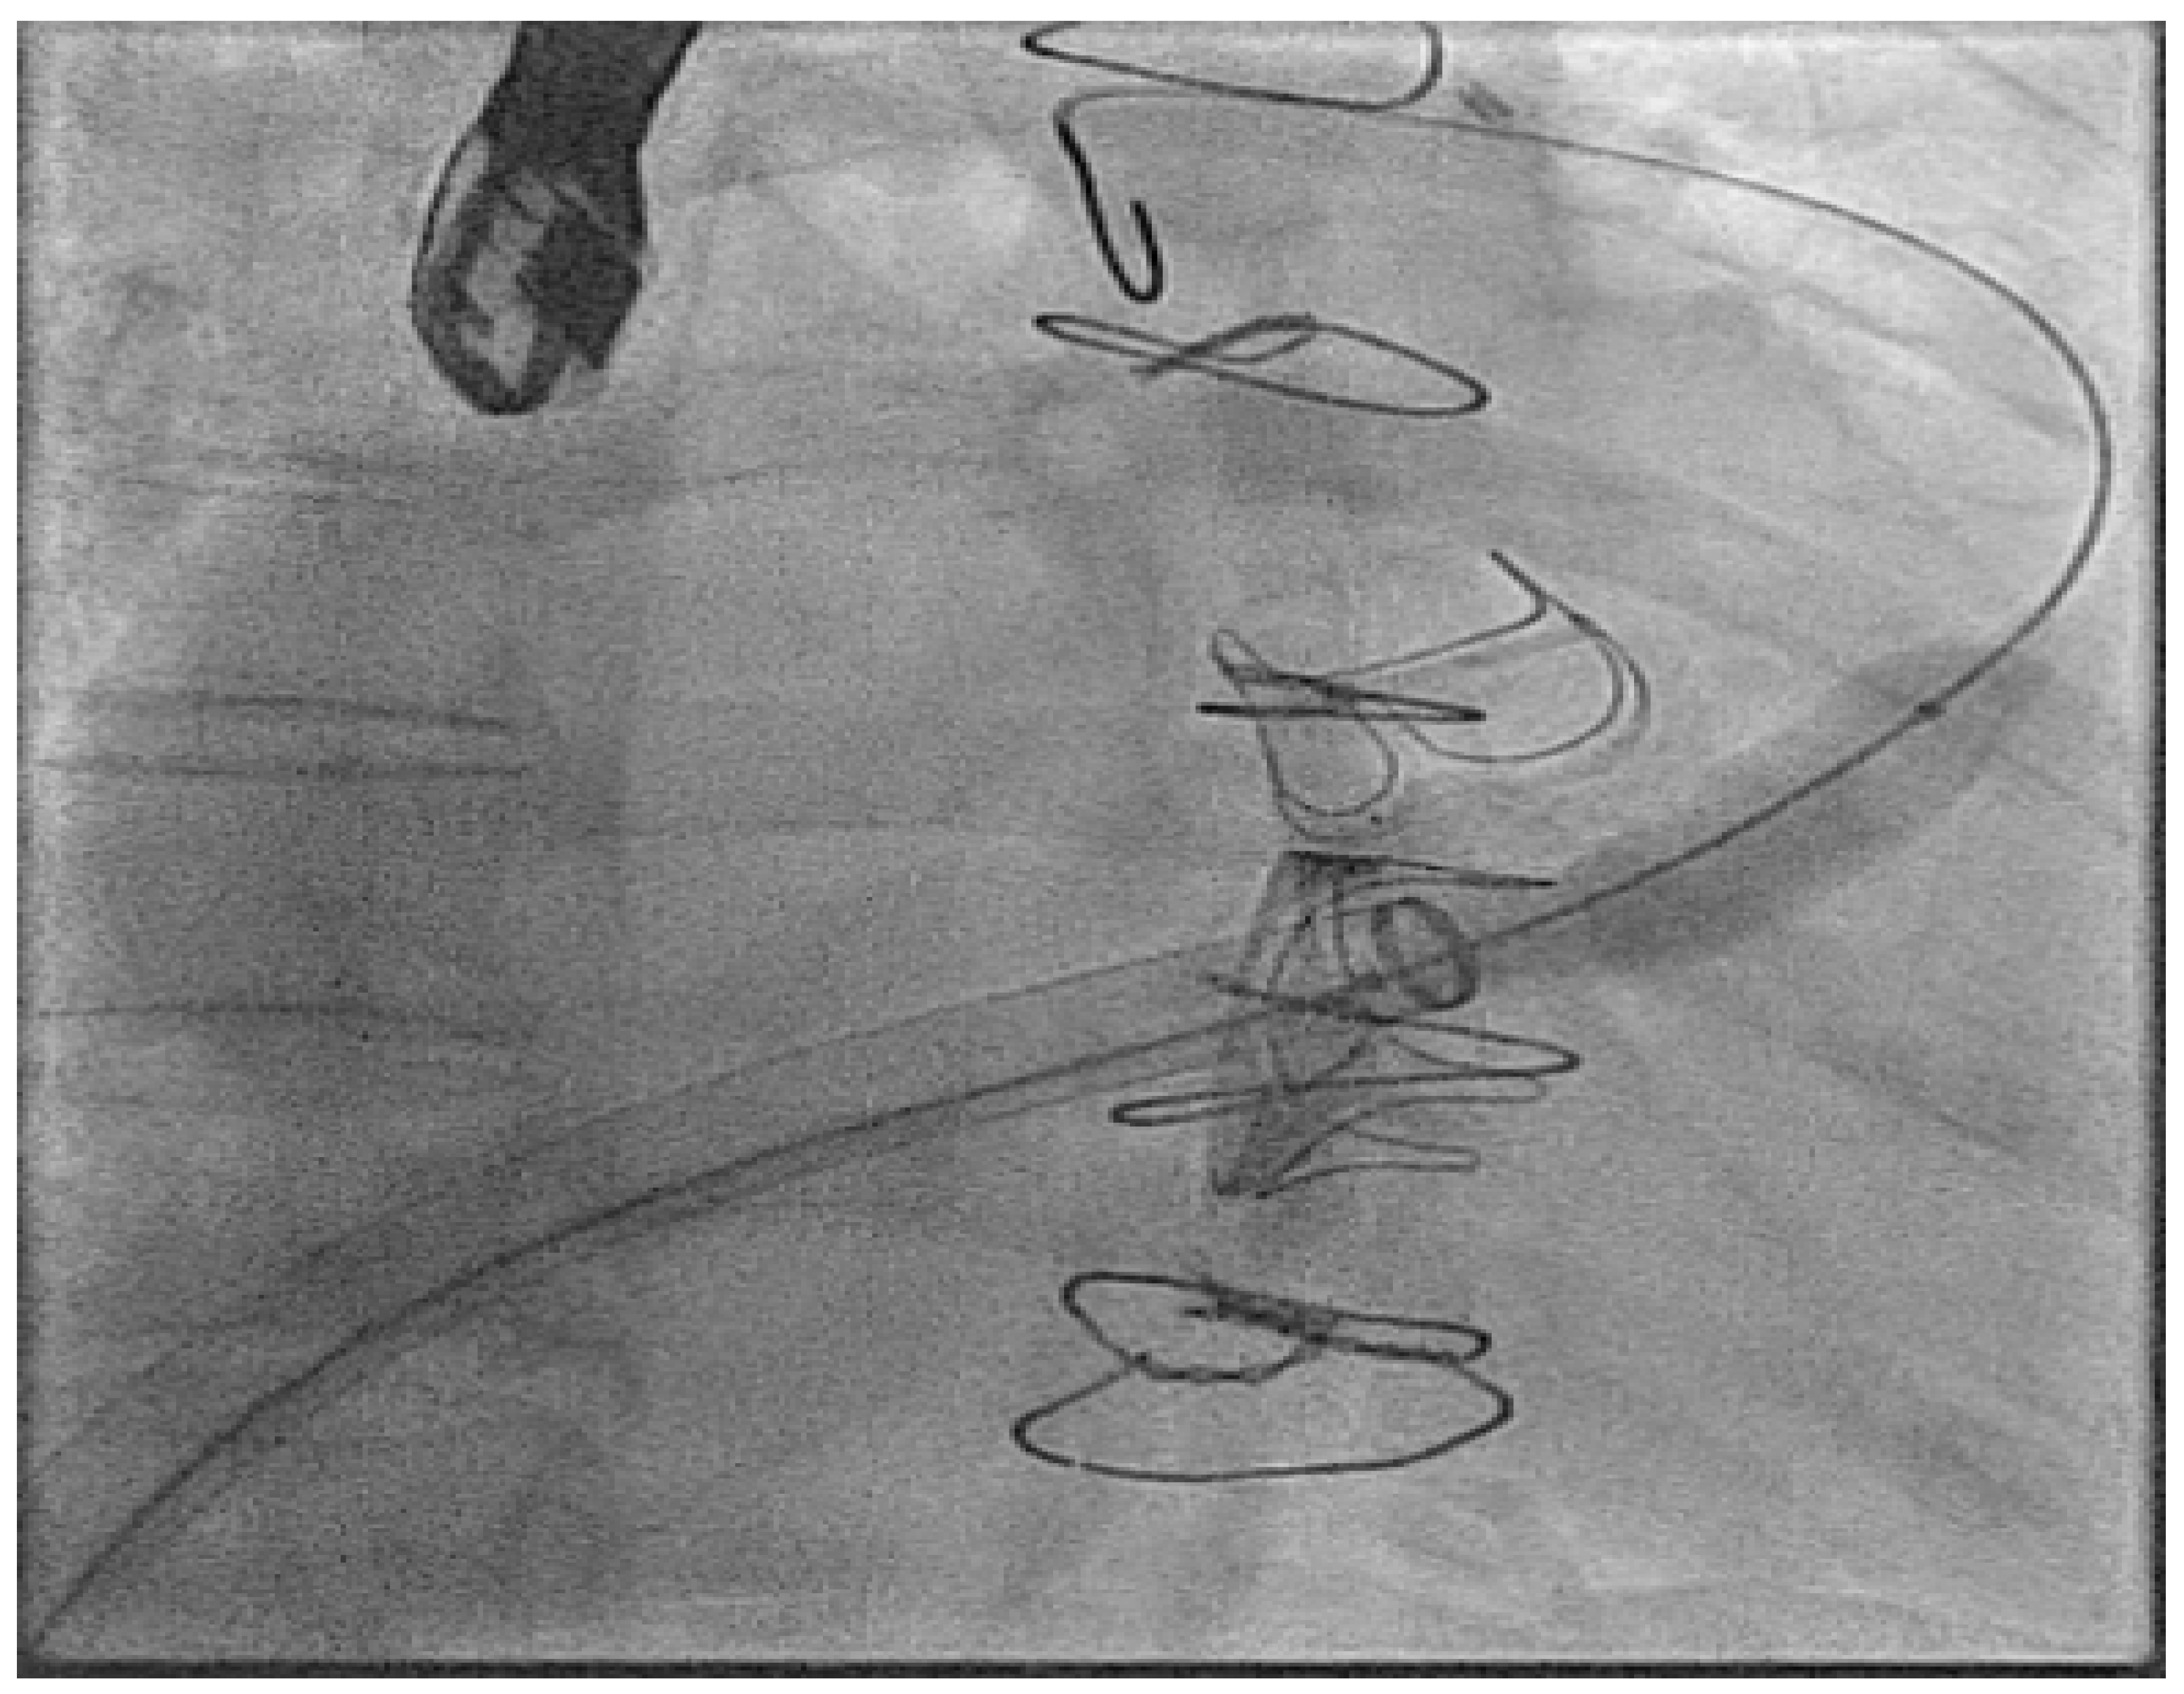

- Hayle, P.; Altayeb, F.; Hale, A.; Rao, A.; Ashrafi, R. Case report demonstrating novel approaches for leadless pacemaker implantation in the single ventricle heart. Eur. Heart J. Case Rep. 2025, 9, ytaf146. [Google Scholar] [CrossRef]

- Goulden, C.J.; Khanra, D.; Llewellyn, J.; Rao, A.; Evans, A.; Ashrafi, R. Novel approaches for leadless pacemaker implantation in the extra-cardiac Fontan cohort: Options to avoid leaded systems or epicardial pacing. J. Cardiovasc. Electrophysiol. 2023, 34, 2386–2392. [Google Scholar] [CrossRef]